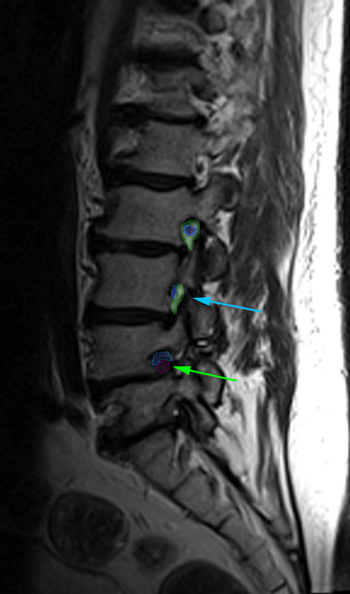

SpinalStenosis2 ForamenStenosis

Αριστερά: Στένωση οσφυϊκού σπονδυλικού σωλήνα. Δεξιά:Φυσιολογικό νευρικό τρήμα στην κορυφή (πράσινο) με ελεύθερο νεύρο στο κέντρο (μπλέ περίγραμμα). Στενό τρήμα (κυανό βέλος) και ουσιαστικά κλειστό τρήμα,το οποίο εμπεριέχει μόνο το πιεσμένο νεύρο (πράσινο βέλος). Τεμάχιο δισκοκήλης εντός του τρήματος (κόκκινο περίγραμμα).